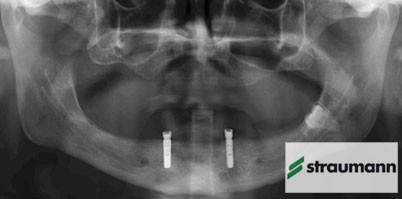

Foto: Straumann

Die durchmesserreduzierten Roxolid-Implantate der Firma Straumann sind eine zuverlässige Alternative zu Implantaten aus Titan Grad 4 und lassen sich für ein breiteres klinisches Behandlungsspektrum einsetzen. So lautet das eindeutige Ergebnis einer umfangreichen Multicenter-Studie nach einem Jahr. Die Studie wurde mit dem Ziel fortgesetzt, weitere Parameter wie Weichgewebe- und Knochenerhalt sowie Implantat-Erfolgsquoten und prothetischen Erfolg zu erforschen. Das positive Ergebnis: Die Zwei-Jahres-Daten bestätigen die Ein-Jahres-Daten.1 Darüber hinaus zeigte sich im direkten Vergleich, dass Roxolid-Implantate mit 98,8 % eine noch höhere Überlebensrate als Titan Grad 4 Implantate (97,5 %) haben. In keiner Gruppe gab es signifikante Unterschiede zwischen der Überlebensrate nach ein und zwei Jahren. Bei der Veränderung des periimplantären Knochenniveaus, dem Sulkus-Blutungs-Index und dem Plaque-Index stellten sich ebenfalls keine bedeutsamen Differenzen zwischen den Gruppen heraus.

Laut Straumann handelt es sich bei der in acht europäischen Studienzentren durchgeführten RCCT-Doppelblindstudie (RCCT: randomisierte, kontrollierte, klinische Studie) um die erste Studie überhaupt, die man je in diesem Ausmaß für ein Implantatmaterial vor der Markteinführung durchgeführt hat. Im Rahmen der Studie wurde 91 zahnlosen Patienten jeweils ein Roxolid SLActive Implantat (Testimplantat) und ein Titan SLActive Implantat (Kontrollimplantat) eingesetzt. Ein Jahr nach der Operation wurde die Studie entblindet und die Daten von 178 Implantaten ausgewertet. Bei der Nachkontrolle nach zwei Jahren wurden keine Implantatmisserfolge festgestellt.

Das aus hochwertigem Titan und Zirkonium hergestellte Material Roxolid ist mit der chemisch aktiven, hydrophilen SLActive-Oberfläche versehen. Roxolid wurde entwickelt, um die Behandlungsoptionen für Implantate mit kleinem Durchmesser zu erweitern und das Vertrauen in diese Implantate zu erhöhen. Das Material zeigt eine höhere Zug- und Ermüdungsfestigkeit als reines Titan und besitzt exzellente Eigenschaften für die Osseointegration.2